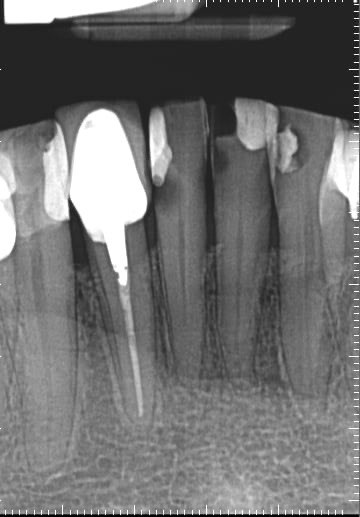

Question 1: What materials cannot be seen in the print of the X ray?

Question2: Which surface shows overhang?

Question 3: Which option is not evident on the print of the X ray?

Question 4: Which options cannot be seen in the print of the X ray?

Question 5: What options cannot be selected for tooth # 4.6?

Question 6: What options cannot be seen in the print of the X ray?

Question 7: What option cannot be identified on the print of the X ray?

Question 8: What condition can be seen in the X ray?

Question 9: Which option cannot be seen in the lower jaw?

Question 10: Which option can be selected for the following X ray?